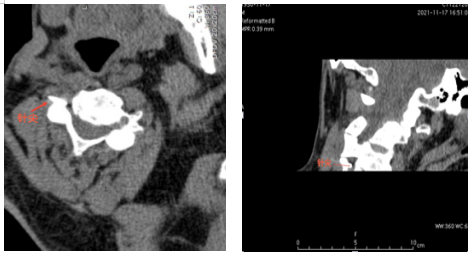

为了确保手术安全顺利进行,术前杨庆红主任组织科室充分讨论病例,制定了详细的手术方案。11月21日,在放射科主管技师胡卫的协助下,杨庆红主任带领疼痛科医生李圣洪在CT引导下找准穿刺路径、角度及深度,为李爹爹实施了颈丛神经脉冲射频微创手术,术后当晚,李爹爹就感觉疼痛明显缓解,人也轻松了一大截。目前患者疼痛控制良好,几乎没有疼痛,预计本周内出院。